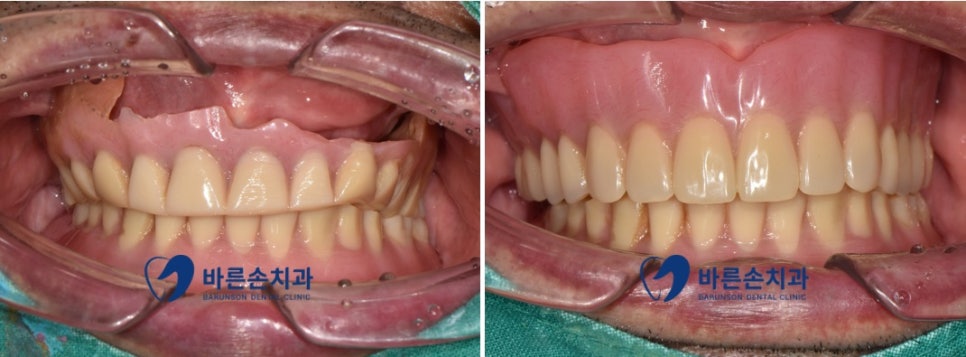

환자분께서는

기존에 이미 위아래 모두 전체 틀니를

사용하고 계셨지만 그중

위에 틀니의 파손으로 인한 불편감으로 저희 치과에 내원해 주셨습니다

기존 틀니에서는 많이 닳아 있던 치아로 인해

무너진 수직 고경 또한

새로 제작을 통해 치료가 되었습니다

전체적인 치료 기간은 한 달이 채 안 걸렸지만

짧은 기간 안에 편안한 식사는 물론 심미적으로도

더 젊어 보이는 효과를 얻었습니다^^